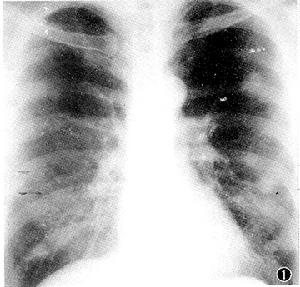

其他輔助檢查:X線檢查早期以不規則小陰影為主,兩肺中下肺野為多,類圓形小陰影少且出現很晚,一般很少出現塊狀大陰影。

肺鐵末沉著病1、形態改變初期為肺野內有密集度較高的不規則影和密度不高的類圓形陰影。

2、斑點沉著期兩肺滿布2~4mm密度高勱邊緣銳利斑點狀陰影,肺門陰影密度高近似金屬塊狀影。

3、肺門金屬塊狀影形成期在肺門第一級支氣管周圍有各種形態沿支氣管排列密度高的塊狀陰影鐵末在支氣管、肺淋巴結的沉著肺功能檢查主要表現為最大通氣量和第一秒時間肺活量較正常人明顯偏低。